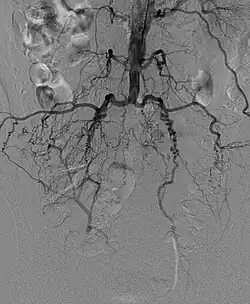

![]() Obraz angiograficzny zespołu Leriche’a | |

Zespół Leriche’a (niedrożność aortalno-biodrowa) – zespół objawów spowodowanych zwężeniem lub niedrożnością końcowego odcinka aorty brzusznej i/lub tętnic biodrowych.